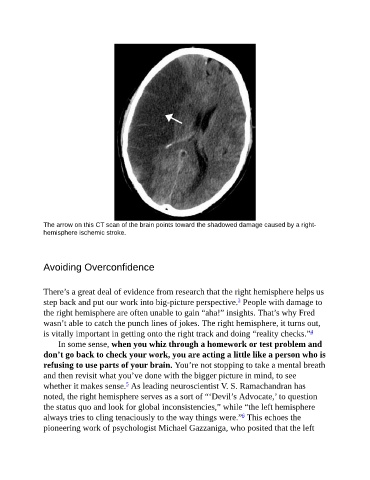

The arrow on this CT scan of the brain points toward the shadowed damage caused by a right-

hemisphere ischemic stroke.